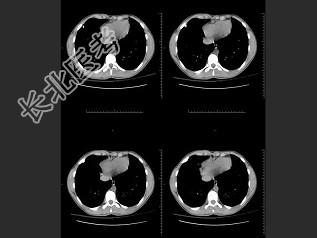

- 单项选择题男,16岁, 咳嗽十余年,结合图像, 最可能的诊断是 ( )

A、胸廓内骨软骨瘤

B、周围型肺癌

C、陈旧性肺结核

D、胸膜粘连

E、以上都不是